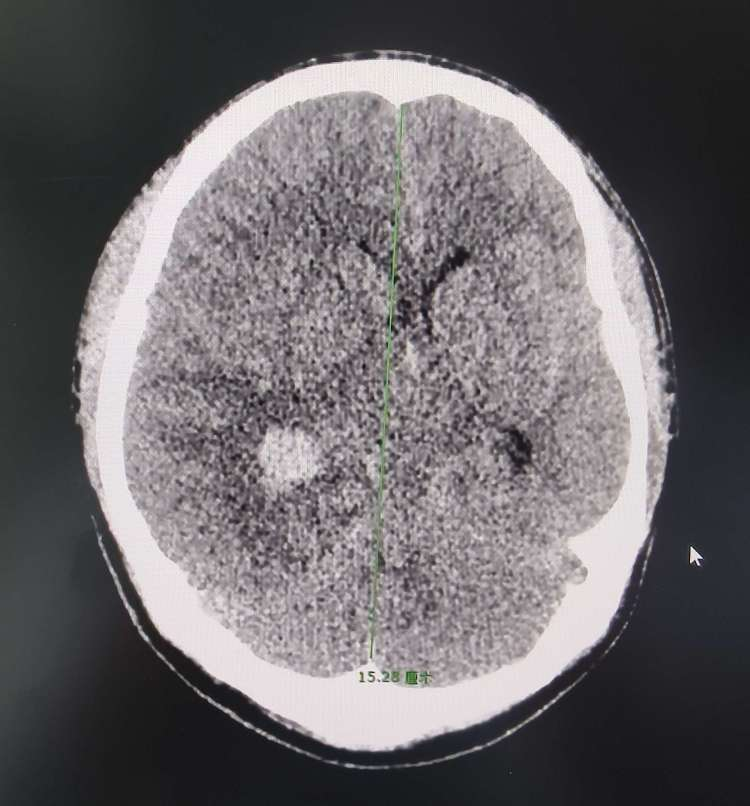

16岁的小曹同学是一名高二学生,在家中上网课时突发头痛、恶心、呕吐,随后意识丧失,家属立即呼叫120送来我院急诊,行头颅CT见:右侧顶枕叶脑出血,约99ml,右侧侧脑室积血,蛛网膜下腔出血。

小朱同学,19岁,是一名刚刚入校的大学生。突然发病,伴恶心、呕吐、意识丧失,立即送来我院,行头颅CT见:右颞叶出血,量约47ml,右侧脑室受压,中线左偏。